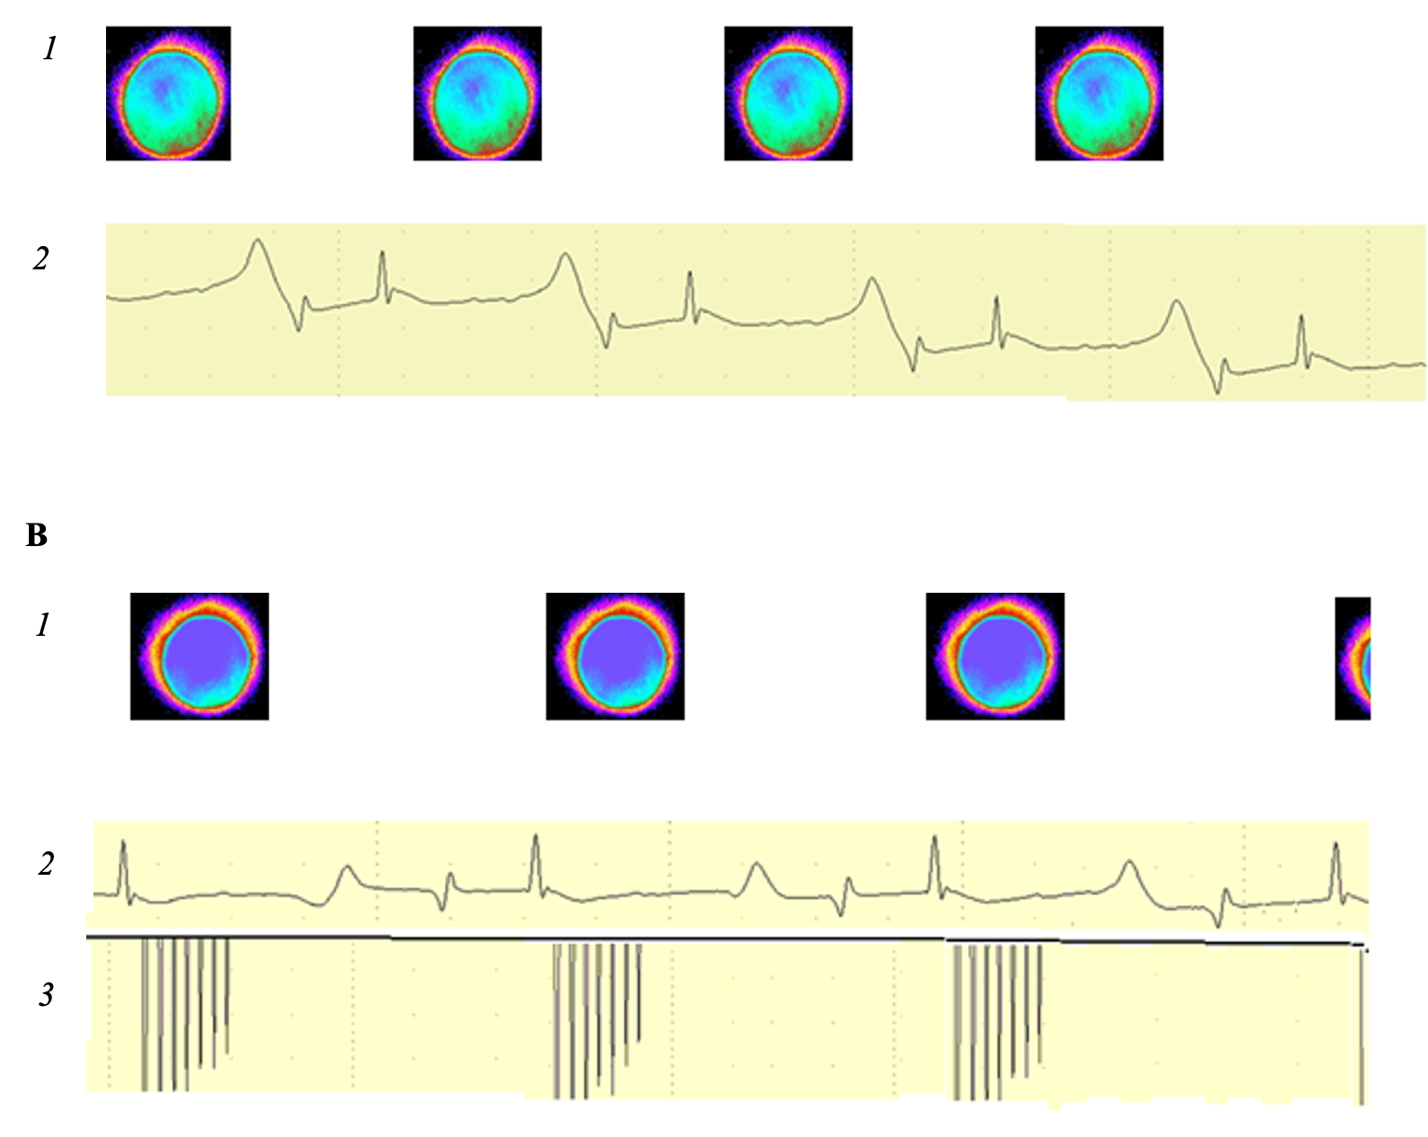

In the first part of experiments, at the initial rhythm in the medulla oblongata of the frog, a focus of luminescence was visualized, synchronous with the heart rhythm, which preceded the V wave (excitation of the venous sinus of the frog’s heart) on the ECG (Fig. 2).

When stimulating the medulla oblongata with volleys of electrical impulses, vagal-cardiac synchronization occurred – for each volley, the heart contracted once. Changing the volley frequency within a certain range caused a synchronous change in the heart rate (HR).

The area of the visualized luminescence zone at vagal-cardiac synchronization was 60.0% greater than that at the initial rhythm (Fig. 2).

Figure 2. Luminescence foci in the medulla oblongata of a frog (1), ECG (2) and volleys of electrical impulses applied to the brain (3). Note: A – initial state; B – vagal-cardiac synchronization.